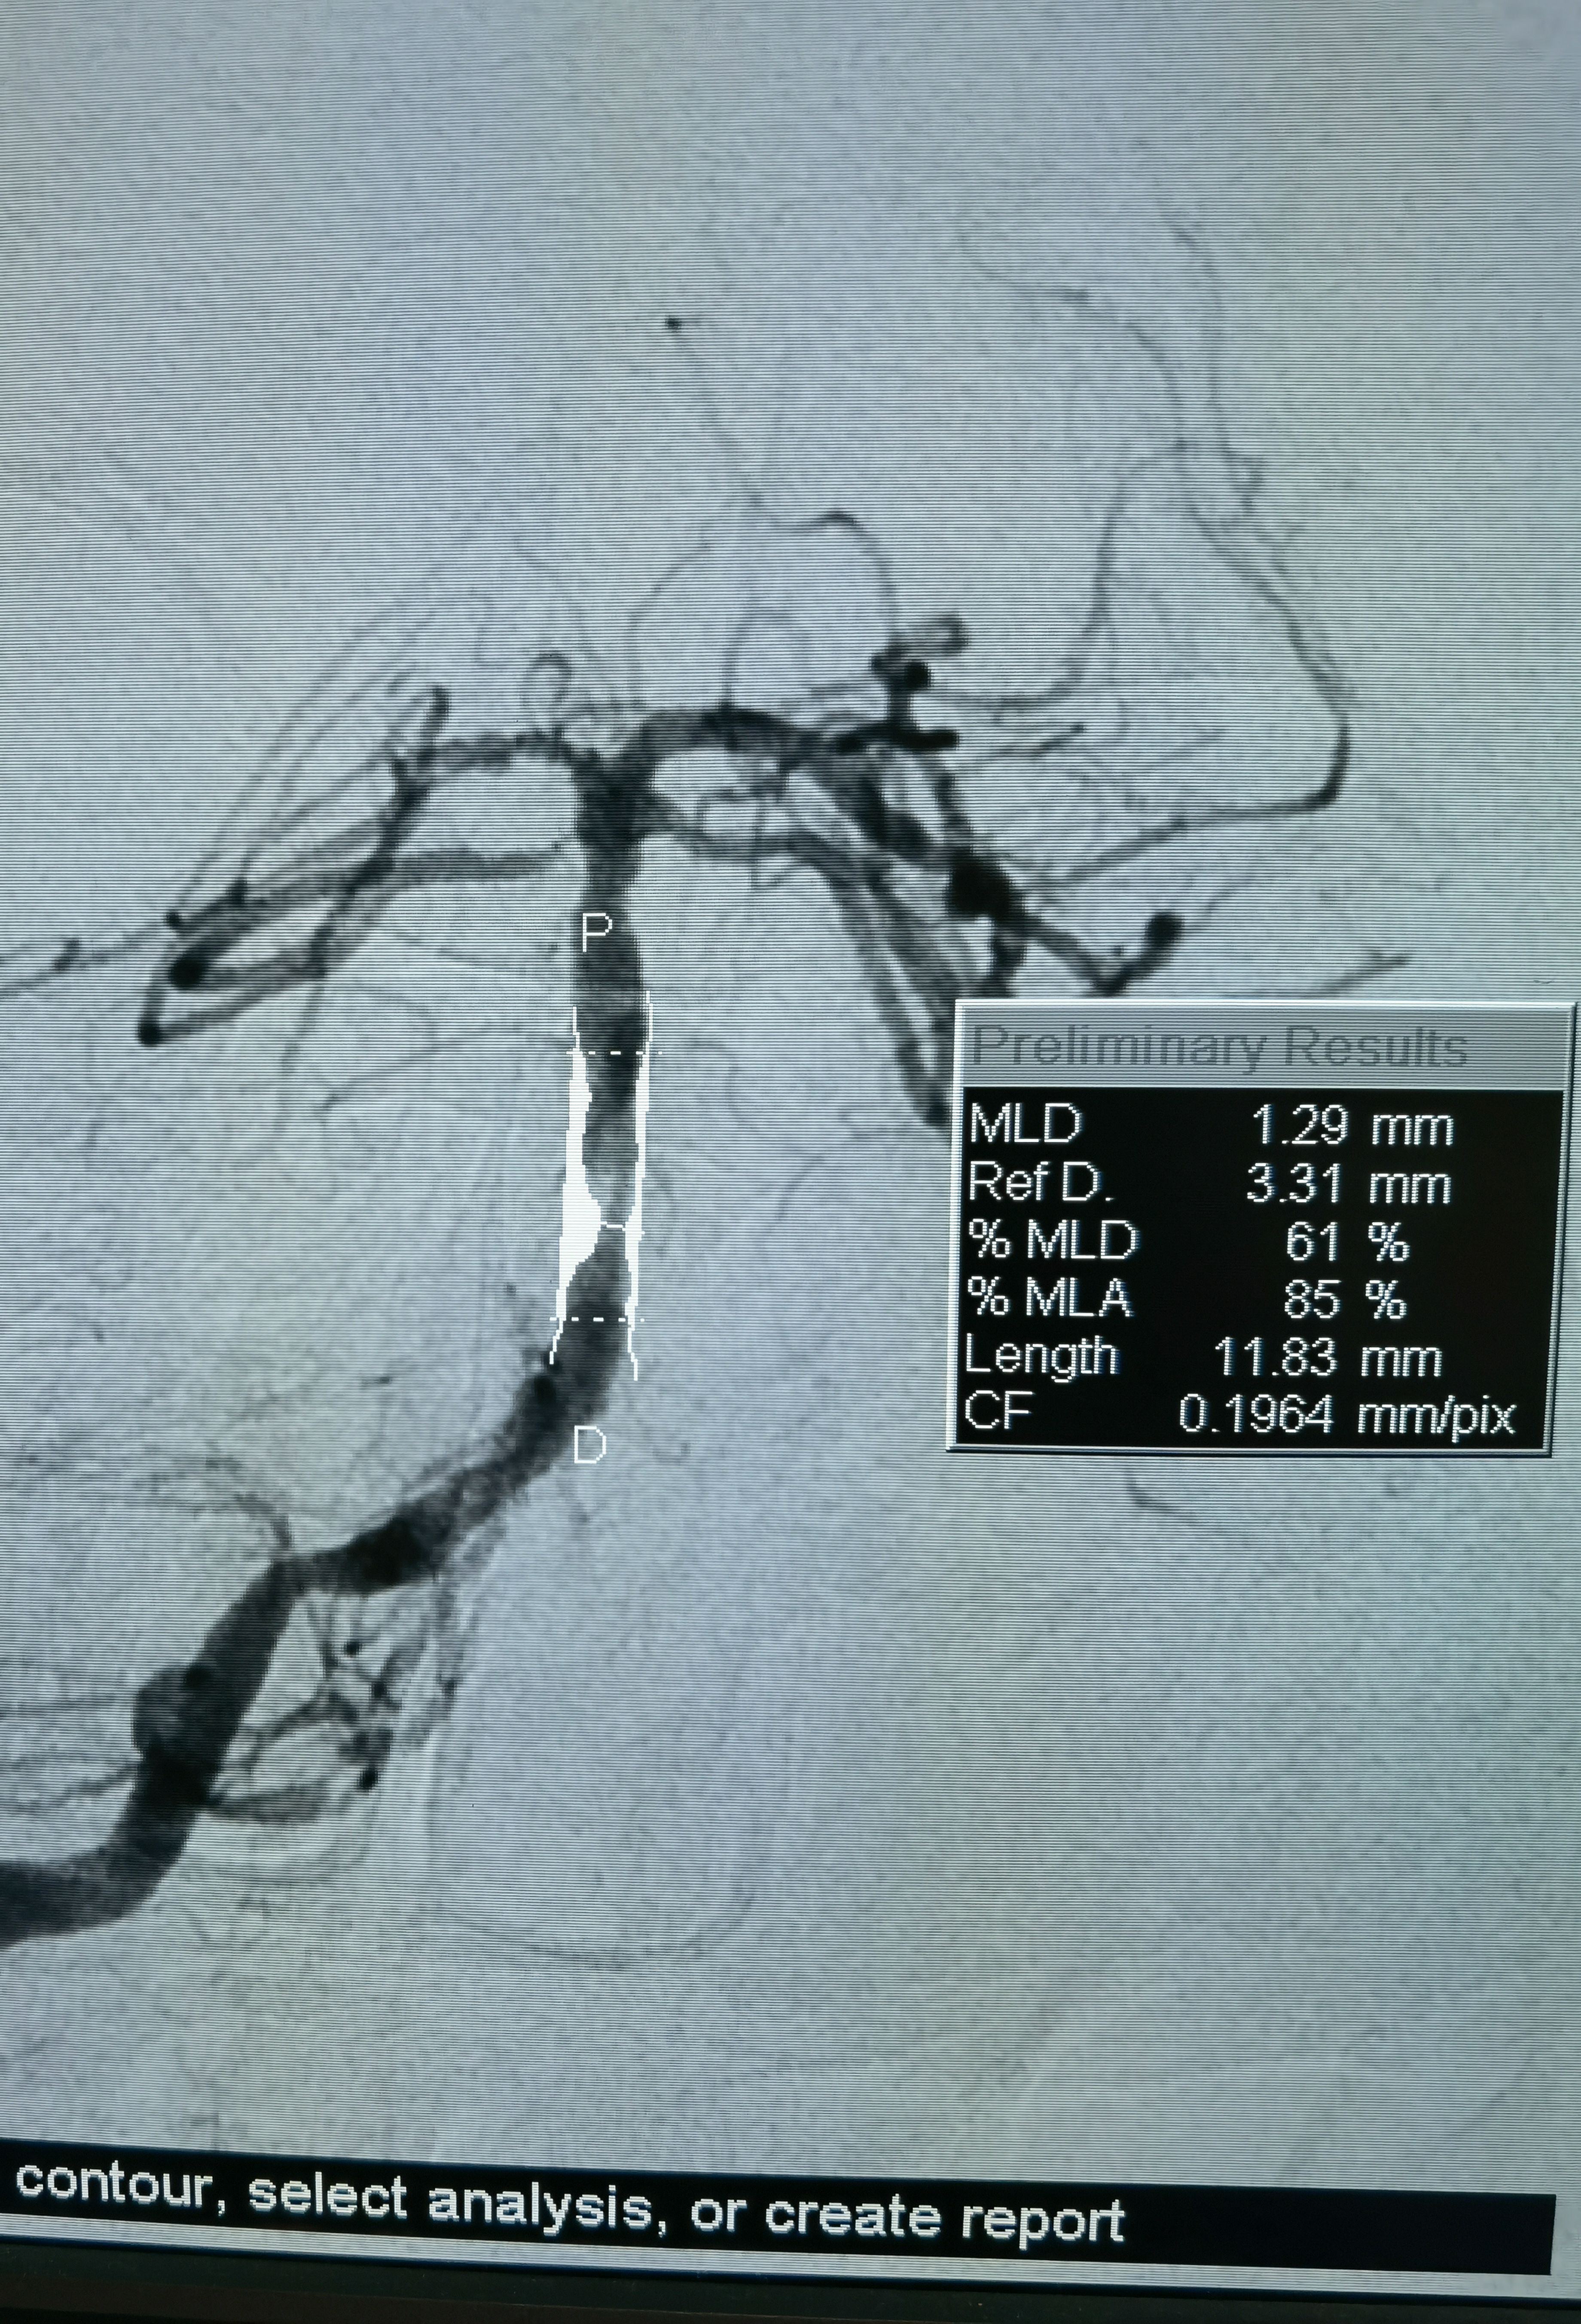

狭窄85%

Gateway2.5*15压力打至8atm

扩张后造影

释放3.5*17Lvis支架